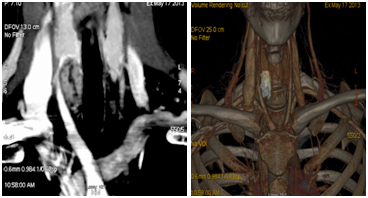

Neck ultrasound (Figure 1A & 1B) revealed a right dominant 2.8cm complex, solid and cystic nodule with intranodular and peripheral vascularity. She was admitted and was treated with intravenous (IV) normal saline. She received 1 dose of IV pamidronate 60mg. Her calcium level improved to 9.8mg/dl and was subsequently discharged. She underwent biopsy of the right thyroid nodule, which was consistent with parathyroid neoplasm possibly adenoma with immunohistochemistry negative for Thyroglobulin, TTF 1, Calcitonin and S 100. She was subsequently referred to endocrine surgery for evaluation of parathyriodectomy. CT scan of neck with 3D imaging reconstruction2 (Figure 2) study confirmed a large well defined nodule with peripheral enhancement suspicious for large right parathyroid adenoma. She underwent minimally invasive parathyriodectomy with fluid aspiration and intra-operative PTH levels fell from 289 pg/ml to 15.8 pg/ml. Pathology (Figure 3) was supportive of the diagnosis of atypical parathyroid adenoma with fragments of hyper cellular parathyroid neoplasm consisting of neoplastic cells with solid nest and trabecular growth patterns with focal capsular distortion and increased mitotic activity. Immunohistochemistry revealed Ki-67 proliferation index 1-3%, bcl-2 positive, diffuse strong and focal weak positive p 53. Post operatively; she was started on calcium and vitamin D supplementation. She is doing well and remains normocalcemic for 2 years following surgical resection with most recent calcium of 9.3mg/dl.

Figure 2 Localization of parathyroid adenoma on CT of neck with 3 D reconstruction.